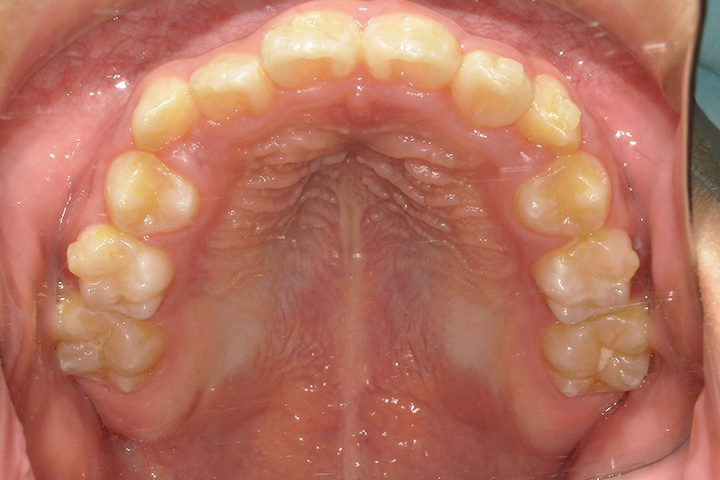

事前の検査は治療の成否を分ける最も重要な工程になりますので、側面・正面セファロ、パントモ撮影、上下顎型取り、口腔内写真、噛み合わせの確認など精密に検査します。必要に応じてCT検査も行い立体的に患者様の口腔内状況を診査・診断します。